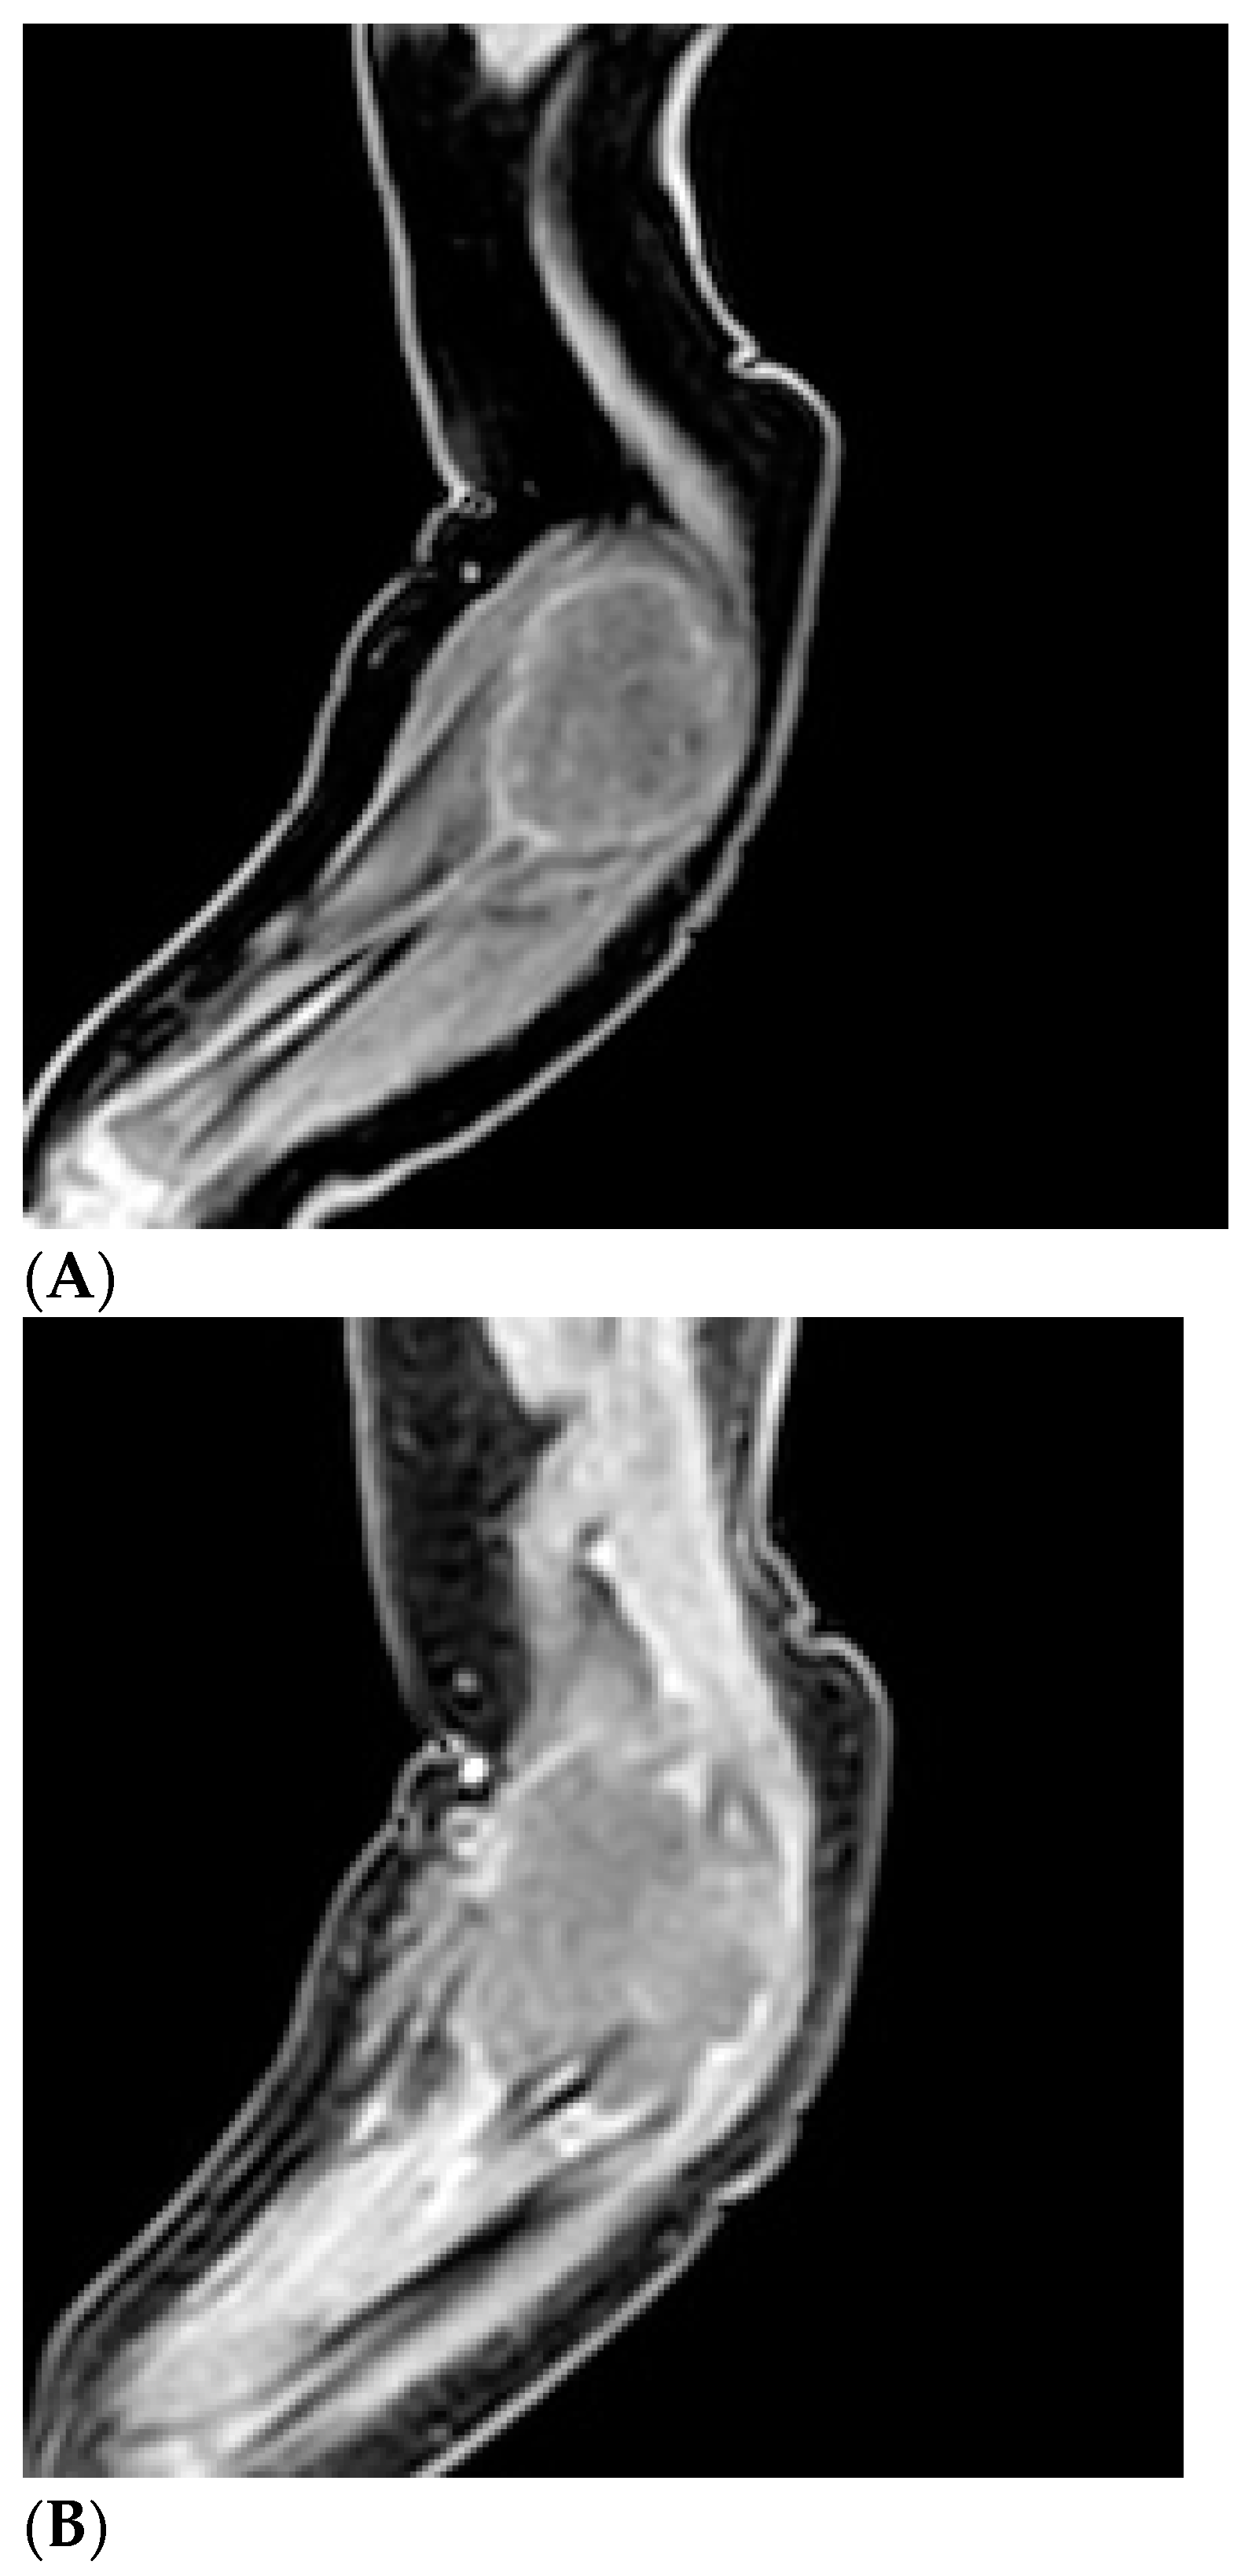

Figure 4.

Preoperative magnetic resonance imaging: presence of an expansive lesion of the anterolateral compartment of the right elbow with the myotendinous junction of the brachialis muscle as its epicenter, until it incorporates the proximal radius, partially eroding it. This lesion has welldefined margins with alteration of the signal of the surrounding soft tissues: hypointense on T1 (A) and hyperintense on T2 (B) and predominantly peripheral lesion impregnation.